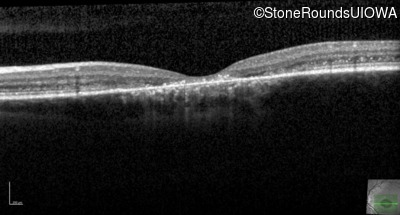

Optical Coherence Tomography - Right - 20/80 -2 sc

Exemplar / OCT Stack